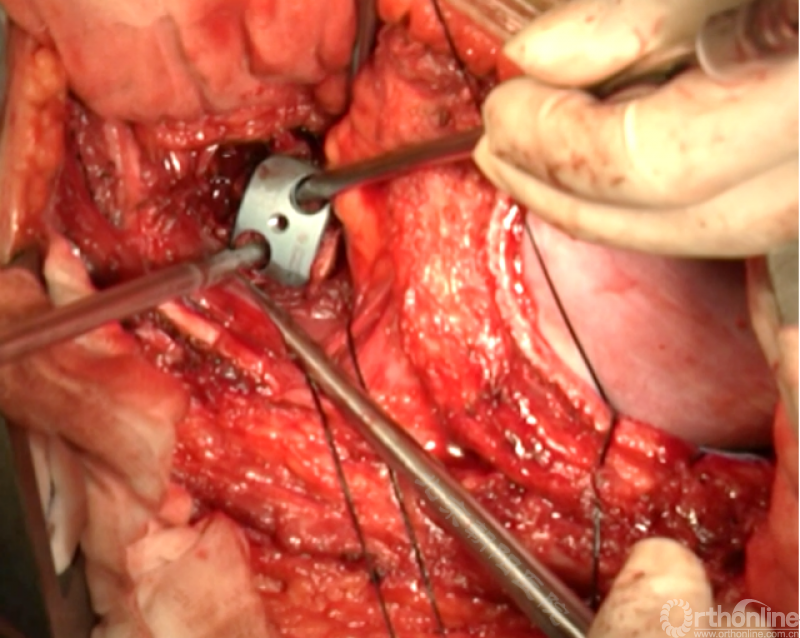

内固定选择的是5.5mm双棒系统,先置入顶椎的螺钉垫板。

置入顶椎的椎体螺钉,螺钉可置入椎体中部到后方1/3之间的范围内。

使用双棒系统时,先置入背侧的螺钉,螺钉指向椎体中线,后置入腹侧的螺钉,螺钉轻度指向后侧。形成对椎体的三角形抓持力。

胸腔侧、腹腔侧螺钉全部置入后,骨移植物植人的越靠近后纵韧带或者纤维环的后缘越好。

将预先折弯的金属棒先置入背侧。